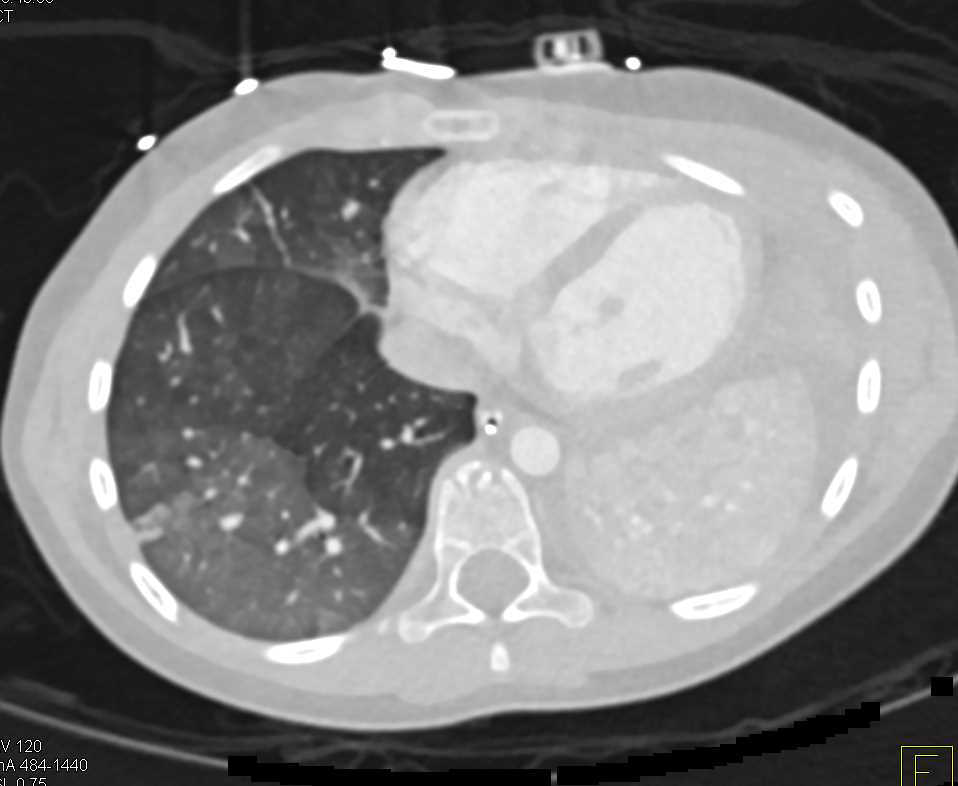

Superior Vena Cava (SVC) Syndrome with Multiple Collaterals in Chest Wall and Abdomen